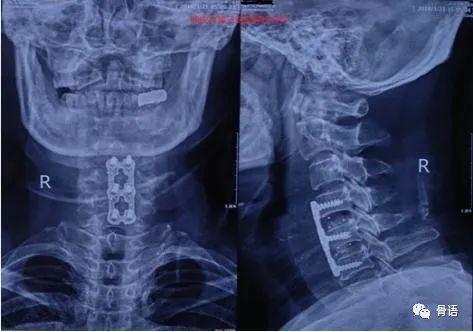

前路手术方式包括前路椎间盘切除减压融合术(anteriorcervical discectomy with fusion,ACDF)、前路椎体切除减压融合术(anterior cervical corpectomy with fusion,ACCF)等,后路手术则包括椎板切除及各种椎管扩大成形术[6-7],此外,还有前后路联合手术及其他未广泛开展的术式。手术方式的选择,需根据患者症状、体征、影像学表现等进行具体分析[8]。

游离颈阔肌皮瓣,经胸锁乳突肌内侧间隙、颈动脉鞘与气管食管之间的间隙进入椎前,切开椎前筋膜,即可显示椎间盘和椎体,采用透视定位椎间隙水平,切除椎间盘,必要时切除后骨刺、肥厚或者骨化的后纵韧带,在椎体间植入自体髂骨块,椎前放置引流,关闭伤口。该术式可以解决①椎间隙狭窄患者间盘和后骨刺、后纵韧带切除困难,②椎体间后凸畸形无法矫形,③由于椎间隙无法撑开不能植入所需高度的植骨块。

2)ACCF

基本手术方法同上,术中切除椎体是松质骨可能出血比较明显。减压后重建可以采用自体髂骨块,但更多采用钛网内植入自体椎体碎骨的植骨融合,之后使用螺钉系统固定。优点基本同上,但同时需注意避免①横向上切除不够,使得后方减压不彻底,②椎体次全切除偏向一侧,使得对侧减压不够。